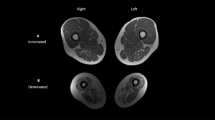

Ten people with motor-complete SCI of at least 2 years duration and 10 people from the general population volunteered to have four DXA-based measurements taken of their femur, tibia and calcaneus. BMDs for seven regions of interest (RIs) were calculated, as were short-term precision (root-mean-square (RMS) standard deviation (g cm−2), RMS-coefficient of variation (RMS-CV, %)) and LSC.

Overall, RMS-CV values were similar between SCI (3.63–10.20%, mean=5.3%) and able-bodied (1.85–5.73%, mean=4%) cohorts, despite lower absolute BMD values at each RIs in those with SCI (35%, heel to 54%, knee; P<0.0001). Precision was highest at the calcaneus and lowest at the femur. Except at the femur, RMS-CV values were under 6%.

For DXA-based estimates of BMD at the distal femur, proximal tibia and calcaneus, these precision values suggest that LSC values >10% are needed to detect differences between treated and untreated groups in studies aimed at reducing bone mineral loss after SCI.